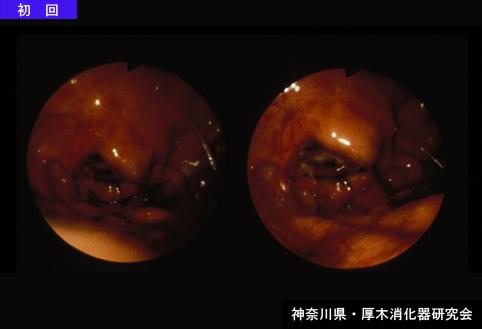

A case of gastrin anisakis mimicking a type IIc early gastric cancer (1980's).

[ Image ID:5807 ]

Gastrointinal Parasite/Anisakis

Stomach/Fundus

Endoscopy

30 - 34